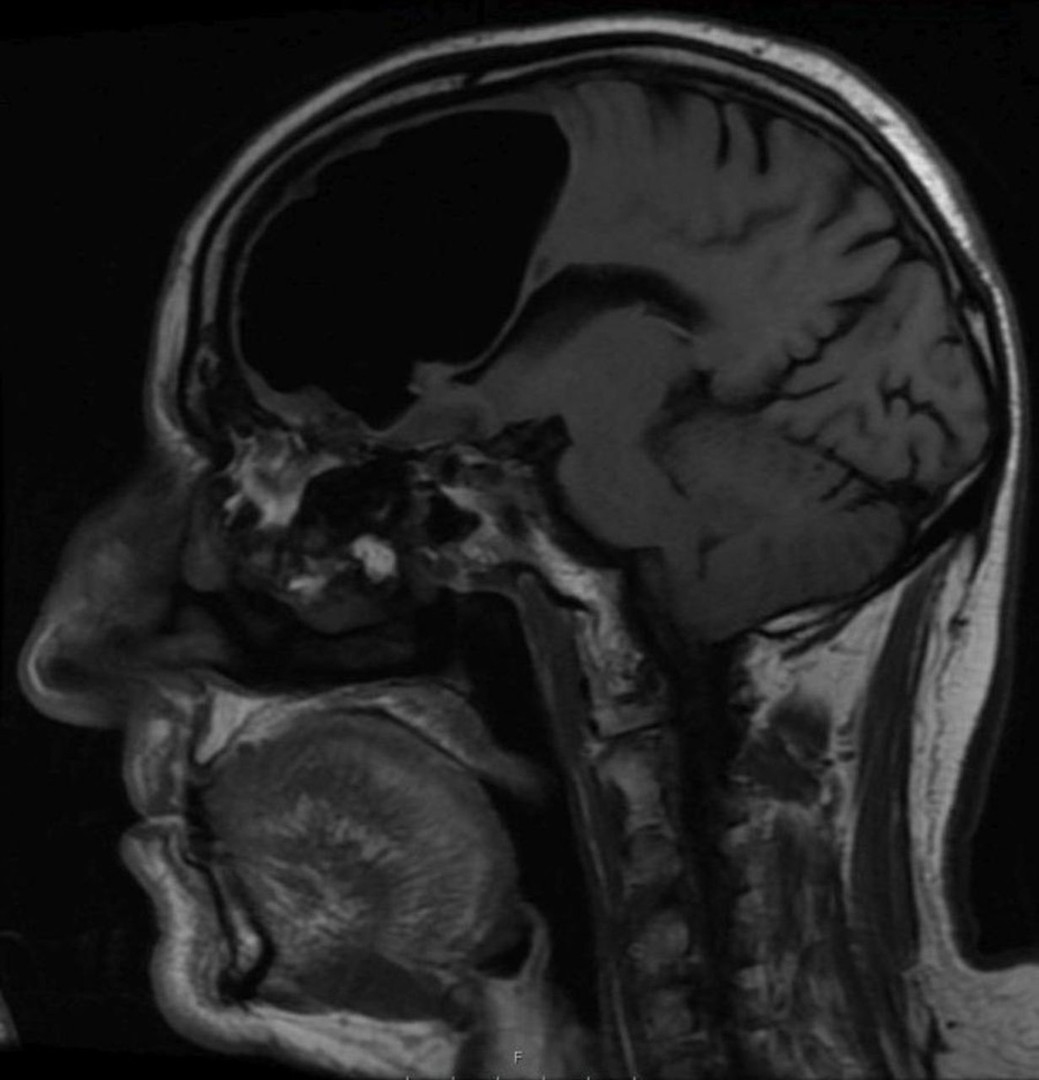

واكتشف الأطباء وجود “تجويف هوائي” يبلغ طوله 10 سنتيمترات في النصف الأيمن من دماغ رجل مسن نقل إلى المستشفى عقب شعوره بالدوار وسقوطه على الأرض، بعد أن تبددت شكوكهم بإصابته بسكتة دماغية.

وبينت نتائج التصوير بالرنين المغناطيسي لدماغ الرجل المسن، وجود ما يسمى بالفتق الهوائي وهو ما يلاحظ عادة لدى المرضى الذين يعانون من إصابات في أجزاء معيّنة من الجسم والأعضاء الداخلية.